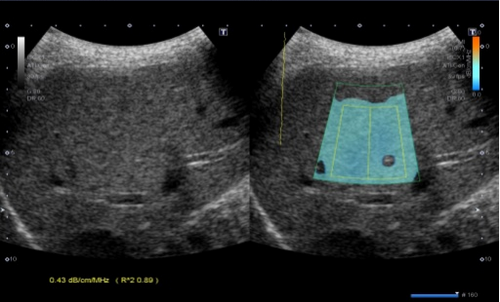

自临床使用以来,检查医生都反应二维图像很清晰,特别是一些新增功能,更受欢迎。1.彩超血流技术除常规CDFI、高级动态血流技术外,还具备超微细血流技术,能检测极低速血流(流速0.1-0.4cm/s),而微细低速血流广泛存在于各类疾病病灶的滋养血流、新生血流,能快速、便捷的帮助超声医生对疾病的准确诊断和鉴别诊断。2.声衰减成像功能,可对肝脏组织的衰减系数进行测量及可视化显示,可以对脂肪肝作出量化诊断,是诊断脂肪肝的有效定量工具。早期发现和量化评估肝脂肪变性,利于及时处理,防止病程进展。3.双平面探头(凸阵+线阵),为前列腺穿刺、肛周脓肿、阴道尿道、盆底功能障碍等疾病的诊断治疗提供不可替代的优势。凸、线双平面探头在前列腺、肛周穿刺活检中,实时快捷观察冠状面、矢状面,确定穿刺针路径、位置,提高穿刺活检成功率。4.浅表微小钙化增强显示技术,显著提升0.1-0.2mm微钙化点的检测识别能力。可以与原始图像实时双幅对比显示,可应用在乳腺、甲状腺等腺体组织恶性肿瘤的早期筛查。5.术中探头,配置穿刺引导架、能提高肝、肾等腹腔脏器的穿刺准确率。